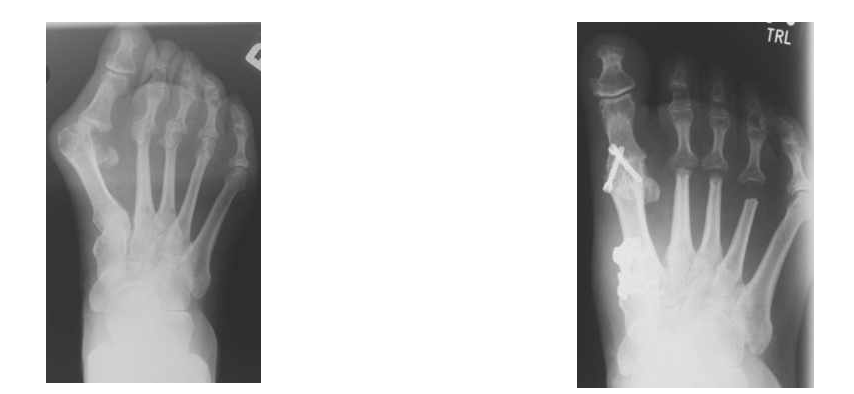

Mittel- und Rückfußchirurgie bei Arthrose

Bei Arthrosen des Mittel- und Rückfußes wird versucht, mit Einlagen und Schuhzurichtungen die Beschwerden zu beeinflussen. Führt dies nicht zur Linderung, so wird die operative Versteifung einzelner Gelenke durchgeführt. Die totalendoprothetische Versorgung des oberen Sprunggelenks wird ebenfalls in unserem Haus angeboten und stellt bei ausgewählten Indikationen (z.B. rheumatoider Arthritis) eine Therapieoption dar.

Rückfußdeformität

Deformitäten wie Knick-Plattfuß und Klumpfuß haben ihre Ursachen im Mittel- und Rückfuß. Bei Schmerzen im Jugend- und Erwachsenenalter wird zuerst versucht, die Beschwerden durch Einlagen, Schuhzurichtungen, ggfs. orthopädisches Schuhwerk zu lindern. Bei Entscheidung zu operativen Maßnahmen wird das Ausmaß der Deformität und der Beschwerden, sowie das Röntgenbild herangezogen. Zur Klumpfußdeformität siehe das entsprechene Kapitel unter Kinderorthopädie.